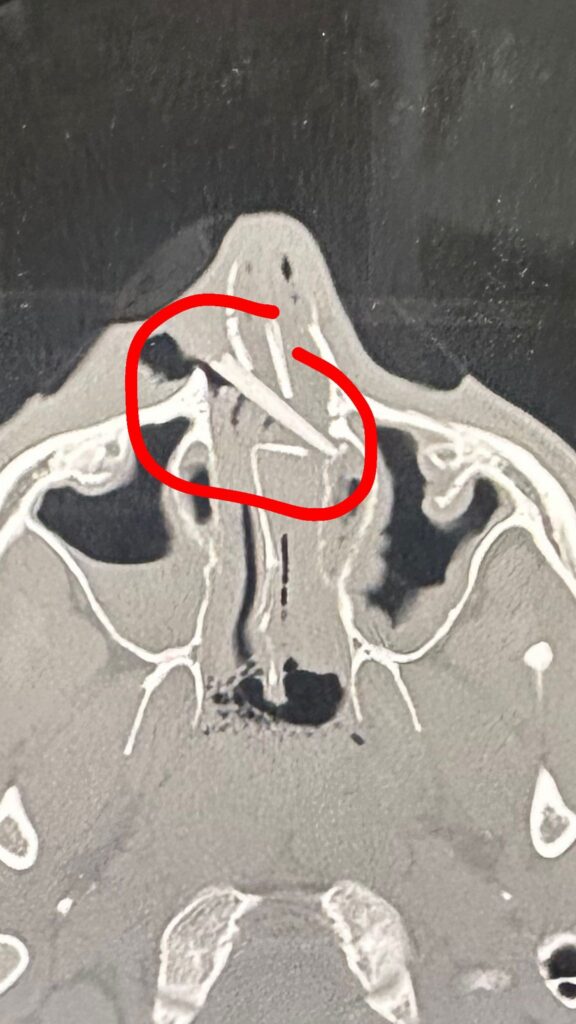

“When the paramedics arrived they were kind of confused.” Davide was taken straight to the nearest hospital, where his face was quickly decorated with ten stitches. He was then put through a CT scanner.

“Some minutes later I was asked if my board was okay,” he said of an interaction with the person operating the scanner. “He told me he could see something really weird in my nose and asked whether I felt anything different.”

Eventually, doctors peered into his nose with a camera and “saw this blue thing,” Davide said. From its colour, it clearly wasn’t bone. “It was crazy, we could see the blue of the fin up on the screen.”

Surgery followed the next day and out came a chunk of fin measuring roughly three centimetres by three. His nose underwent some repair, and his eyesight, by luck, remained intact. “I risked my eye and probably my life too,” he said. “I have a guardian angel for sure.”